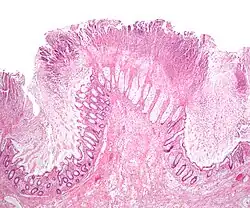

| A micrograph demonstrating cryptitis, a microscopic correlate of colitis. H&E stain. | |

An important investigation in the assessment of colitis is biopsy for histopathology. A very small piece of tissue (usually about 2mm) is removed from the bowel mucosa during endoscopy and examined under the microscope by a histopathologist. A biopsy report generally does not state the diagnosis, but should state any presence of chronic colitis, give an indication of disease activity, as well as state the presence of any epithelial damage (erosions and ulcerations).[6]

Histopathology findings generally associated with chronic colitis include:[6]

Crypt degeneration -

Crypt branching and other architectural distortions -

Paneth cell (pictured) or gastric metaplasia (only applies in the left colon and rectum)

Other findings include basal plasmacytosis and mucin depletion.[6] Histopathology findings generally associated with active colitis include:[6]

-

Neutrophilic cryptitis (neutrophils within crypt epithelium) -

Crypt abscesses (luminal neutrophilic aggregates) -

Gland destruction -

Ulceration (seen here as absence of epithelium, and granulation tissue with many fibroblasts)